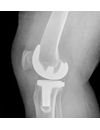

Advances in biomedical implant and device technology continue to present new challenges in the area of physical testing. Particle Size Distribution, Surface Area and Porosity measurement data are invaluable to the biomedical researcher. PTL partners with each client to design projects that provide this needed information while controlling the costs of research. Applications have included particle size analysis of wear particles in fluid submitted from implant fatigue studies and pore size analysis of tricalcium phosphate granules compressed into bone grafting media. Evaluation by photomicroscopy and mercury porosimetry of artifical ligament materials have provided insight to researchers on their products.